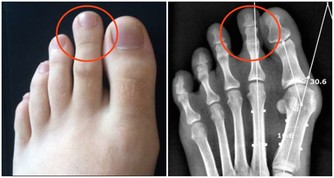

2、眼睛眼睛的保健可以包括各式各樣的問題,其中包括視線模糊、疼痛或紅腫。

在第二和第三腳趾的下方按摩或施加壓力,可減緩這些不適。